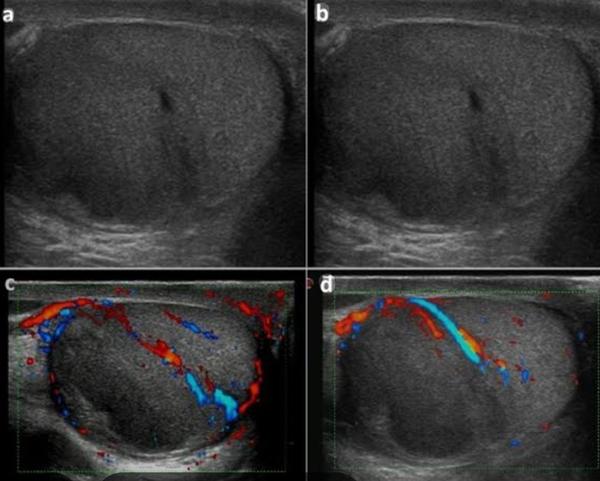

HSG (Hysterosalpingogram ) in rohini delhi

HSG (Hysterosalpingogram ) in rohini delhi HSG test near me C-8/193 sec 8 rohini delhi 9811552...